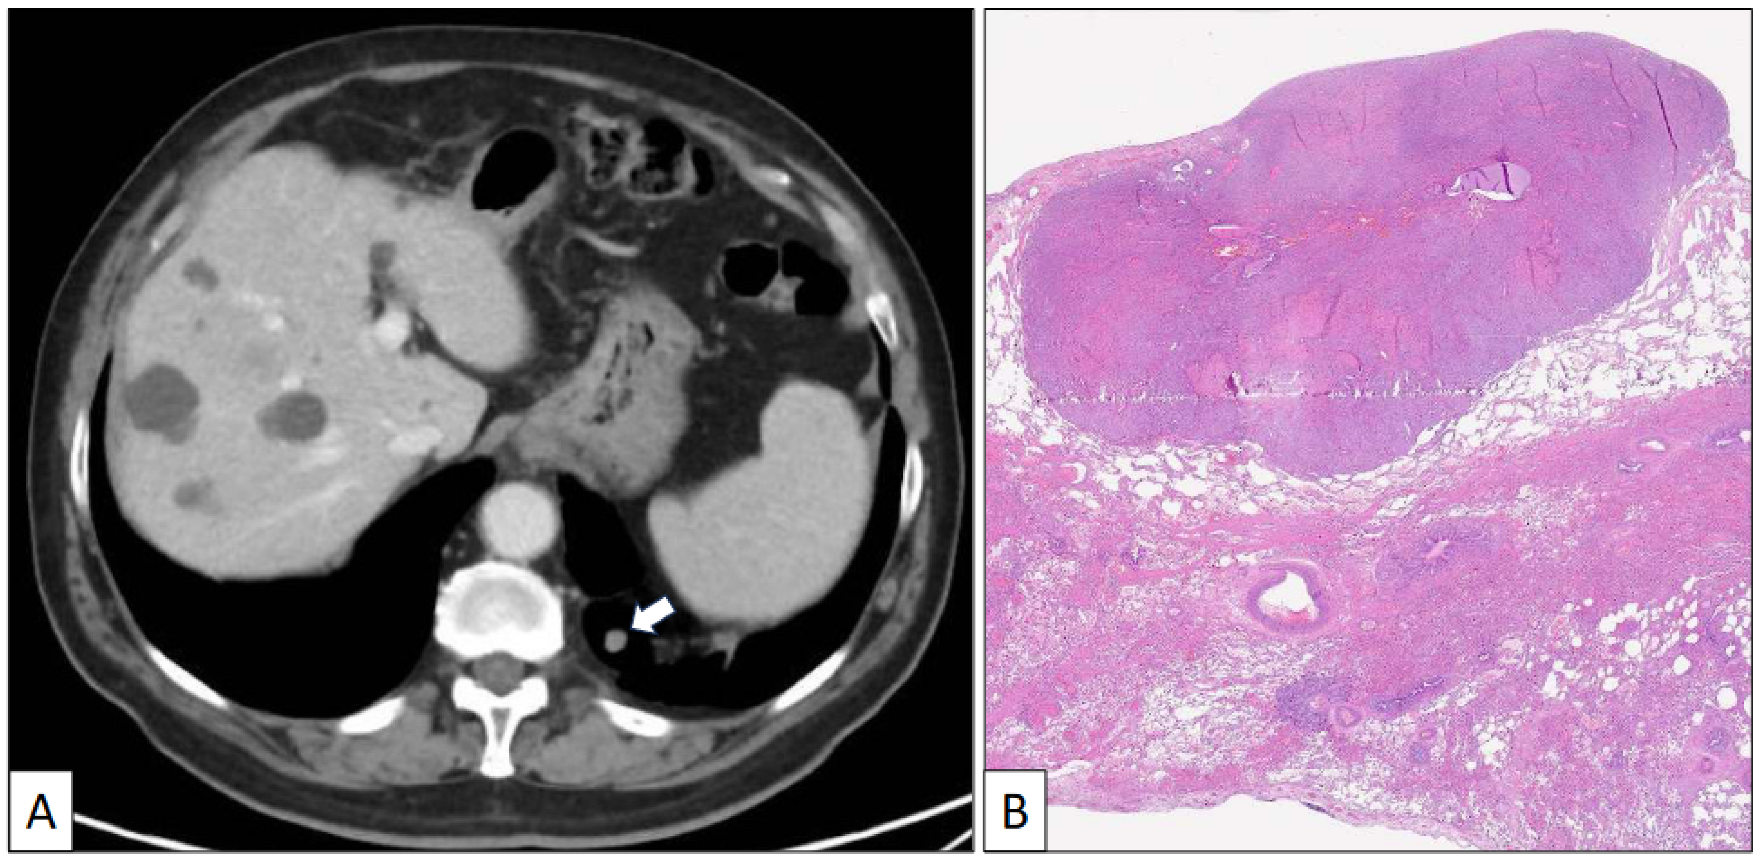

Figure 2.

(A) Axial CT scan image of a left lower nodule close to the costophrenic angle. (B) Histological panoramic view of a well-delimited solid tumor growing beneath the pleural surface (hematoxylin-eosin, original magnification ×1.5).

The atypical left lower lung resection showed a tumor with well-defined limits growing into the lung parenchyma close to the pleura (Figure 2B). The tumor displayed a predominantly dense proliferation of cells with sclerotic (Figure 3A), solid (Figure 3B), and hemorrhagic (Figure 3C) areas. At the tumor periphery, no infiltrative borders were seen and necrosis was not detected. A closer view presented a biphasic cellular pattern with stromal-appearing cells together with surface cells (Figure 4A). No atypia or mitosis was seen. Foamy macrophages were occasionally detected.